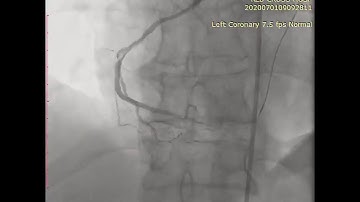

Coronary CTO Revascularization